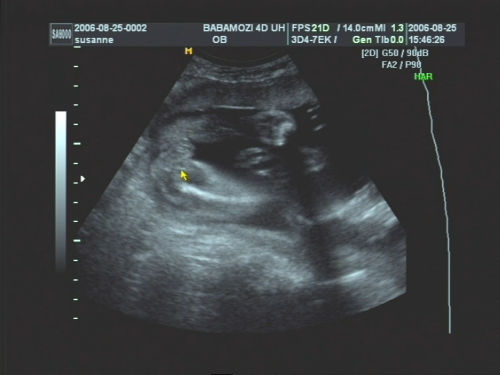

Pár kép:)

És akkor jöjjenek a képek:

Nem tudtam betelni velük,és nem tudtam választani közülük,azért van ilyen sok:

Kép Olyan kis szégyellős volt a drága,hogy állandóan takargatta a szemeit:Kép